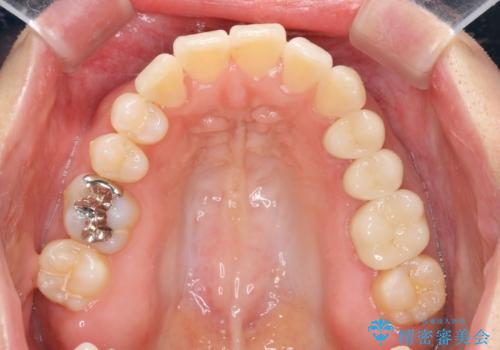

職業柄ワイヤー矯正ができない、マウスピース矯正で行う八重歯抜歯症例

治療に制約がある場合でも、現実的な治療ゴールを設定することで機能的・審美的な歯並びを手に入れることができました。